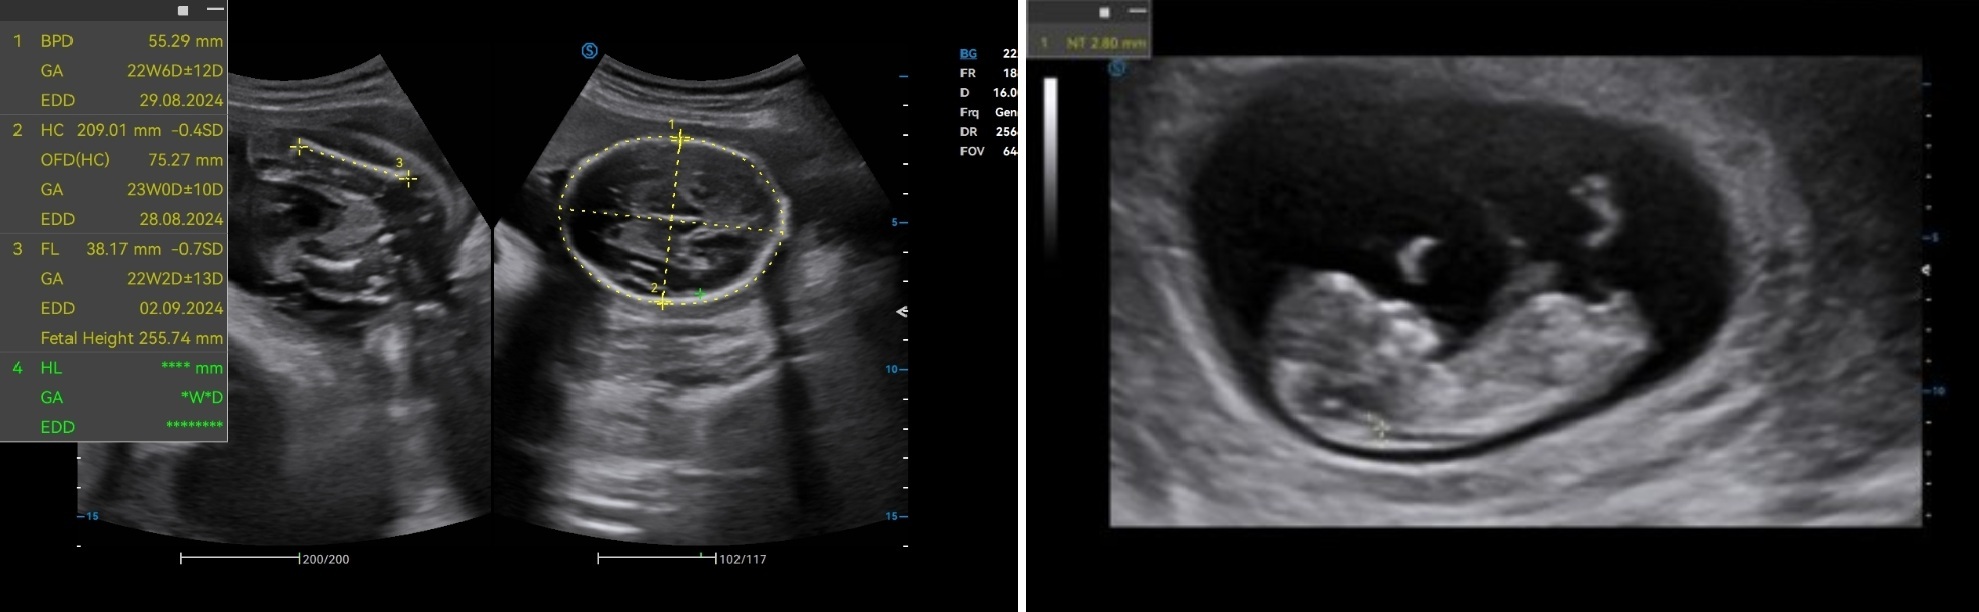

Auto OB automatically measures the common fetal biometric results (HC, BPD, FL, etc.) in standard sections.

Auto NT automatically recognizes and measures the thickness of the fetal nuchal translucency.

Lumi 4D enables the adjustment of light source angle to support real-time static stereo imaging of the fetus.